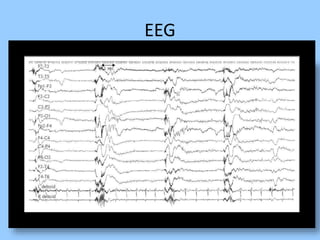

1. The document discusses EEG patterns and findings in various neurological conditions seen in children. It includes descriptions of normal EEG findings as well as abnormal patterns seen in conditions like absence seizures, West syndrome, benign childhood epilepsy with centrotemporal spikes, Lennox-Gastaut syndrome, non-convulsive status epilepticus, subacute sclerosing panencephalitis, and herpes encephalitis.

2. Case studies are presented with clinical histories and EEG findings to illustrate different pathologies. Treatment options are also mentioned for many of the conditions.

3. International standards for EEG electrode placement and recording parameters are reviewed. Characteristics of different EEG waves, amplitudes, and patterns are described.